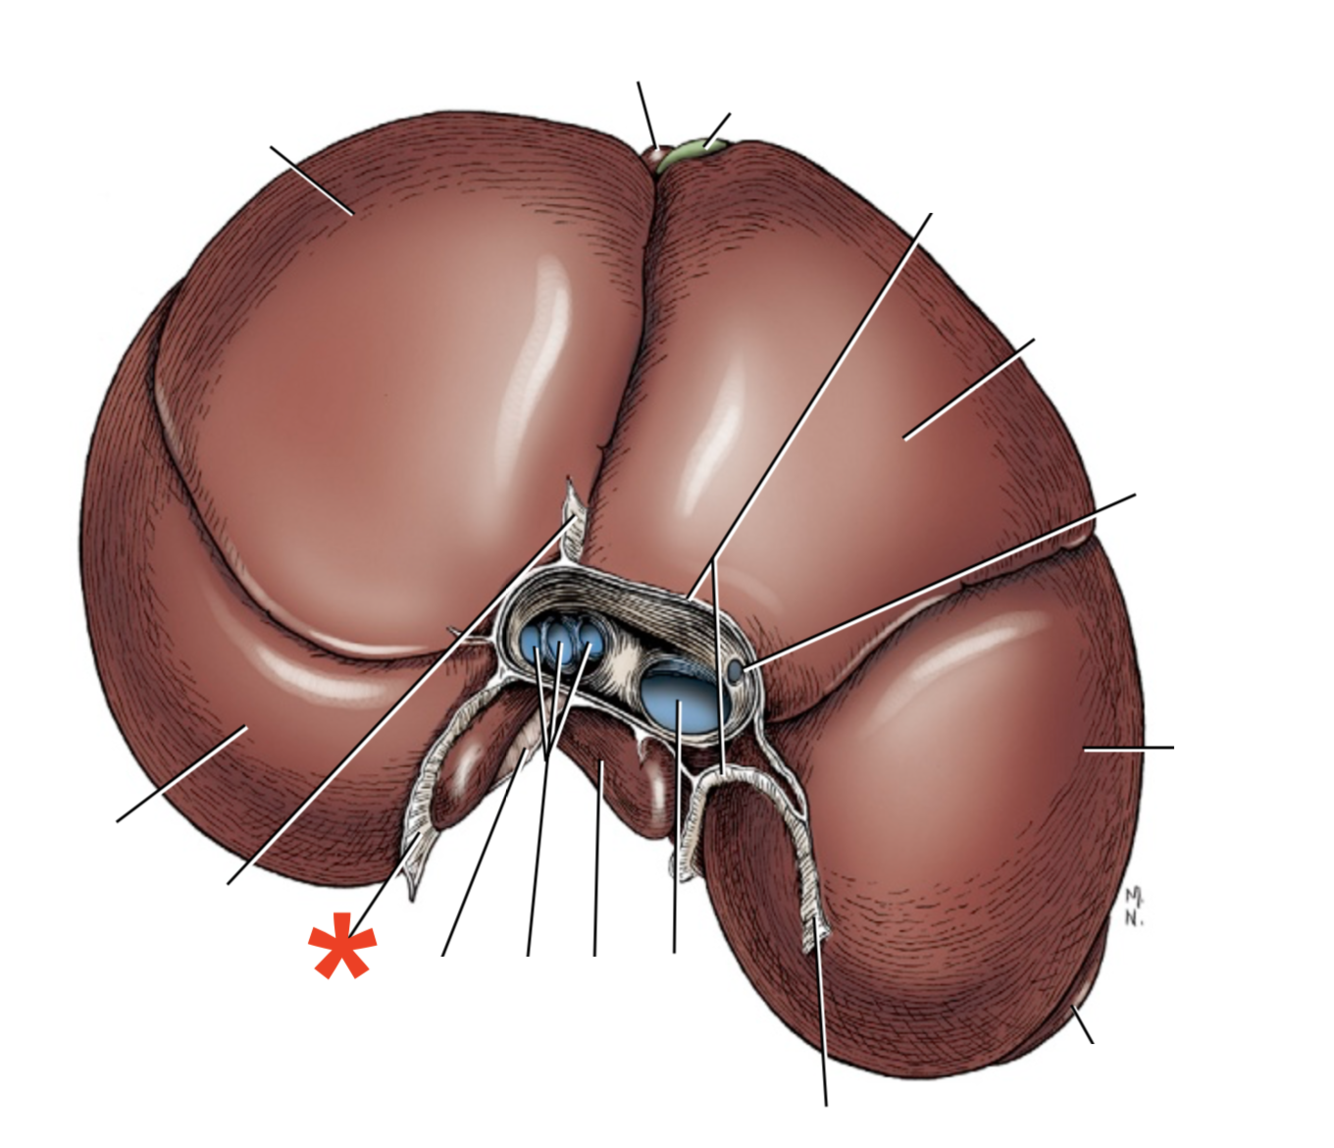

Facies diaphragmatica

What is shown? Give the Aspect

Liver of a Cat

Area nuda

- Not covered by serous membrane

The Caudate Process extends from the…

Lobus caudatus

The sharp-edged border of the liver is called…

Margo acutus

The blunt-edged border of the liver is called…

Margo obtusus

Ligg.falciformehepatiset tereshepatis

18

Lig. coronale hepatis

15

Lig. hepatogastrica

16

Lig. hepatoduodenalis

- Adjacent to ostium pyloricum

Lig. triangulare sinistrum

Lig. triangulare dextrum

Lig. hepatorenale